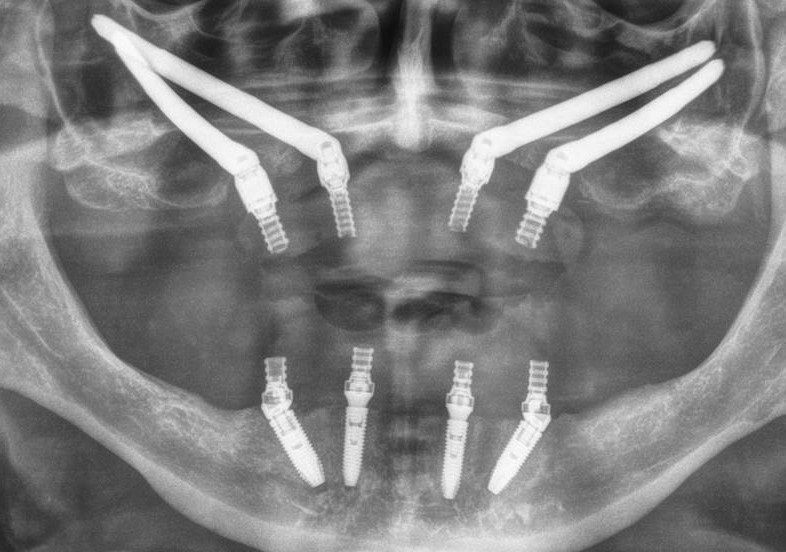

Zygoma-Implantate sind sehr lange Spezial-Implantate, die nicht im Kieferknochen, sondern im Jochbein (Os Zygomaticum) verankert werden und als Basis für festsitzenden Zahnersatz im Oberkiefer dienen.

Das Jochbein weist hingegen von Haus aus eine sehr stabile Knochensubstanz auf und ermöglicht so eine sofortige, sichere Verankerung von Implantaten. Dadurch ist es möglich, im Rahmen einer Sofortversorgung unmittelbar nach dem Setzen der Zygoma-Implantate diese mit festsitzendem Zahnersatz zu versorgen.